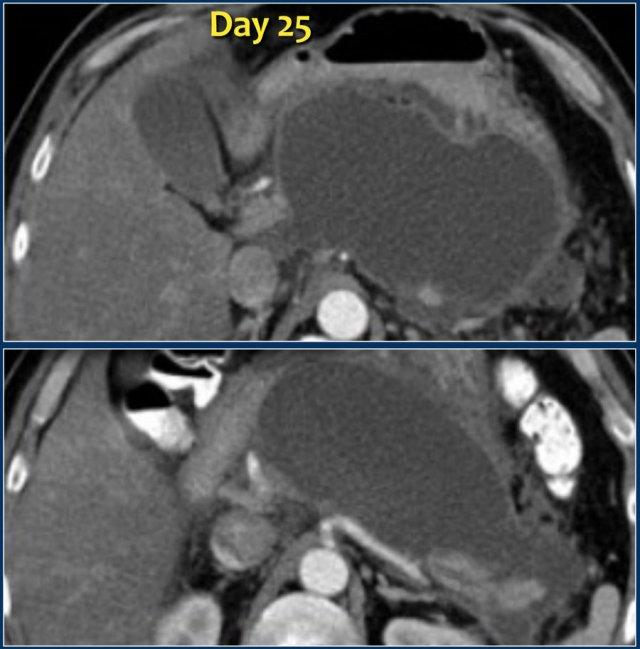

Ổ hoại tử được bao bọc (3)

Đây là hình ảnh một ổ dịch trong và quanh tụy đồng nhất, giới hạn rõ với thành ngấm thuốc, vào ngày thứ 25 của một đợt viêm tụy hoại tử cấp tính.

Bệnh nhân này có sốt và suy đa tạng.

Do đó, ổ dịch này bị nghi ngờ là WON nhiễm trùng chứ không phải nang giả tụy.

Trong phẫu thuật, ổ dịch chứa nhiều mảnh vụn hoại tử, điều này không được thể hiện trên CT.

Các trường hợp này minh họa rằng đôi khi CT không thể phân biệt một cách đáng tin cậy giữa các ổ dịch chỉ chứa dịch thuần túy và các ổ chứa hỗn hợp dịch và mảnh vụn hoại tử dạng đặc, có hoặc không có nhiễm trùng.